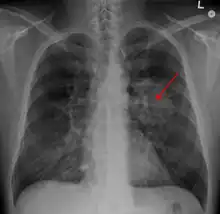

Tumeur du poumon

Radiographie thoracique montrant une masse parahilaire du poumon gauche